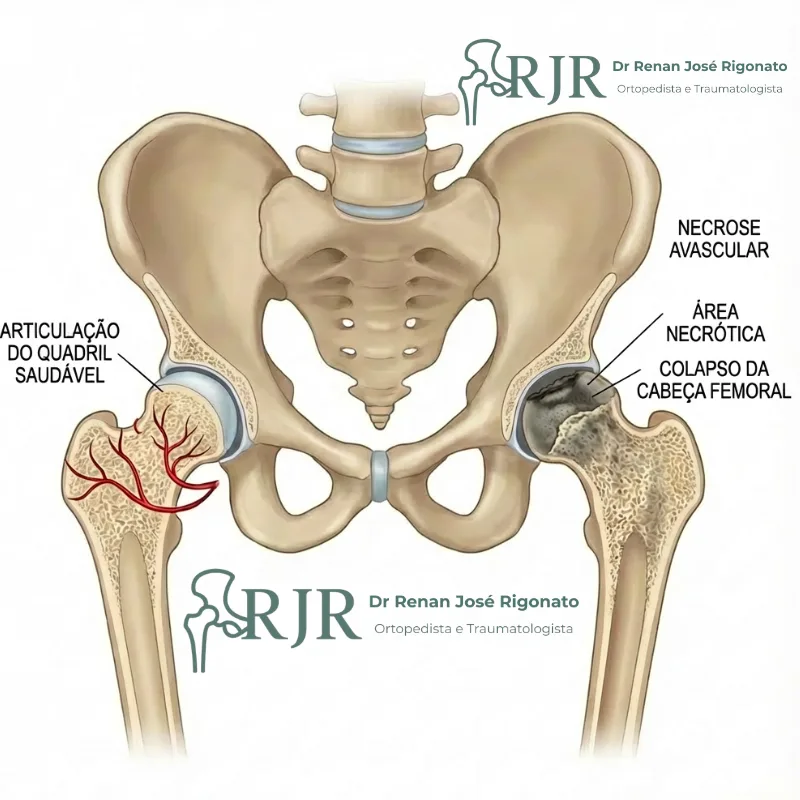

Osteonecrose do fêmur

Condição que compromete a mobilidade do quadril pela falta de circulação. O diagnóstico precoce preserva a articulação.